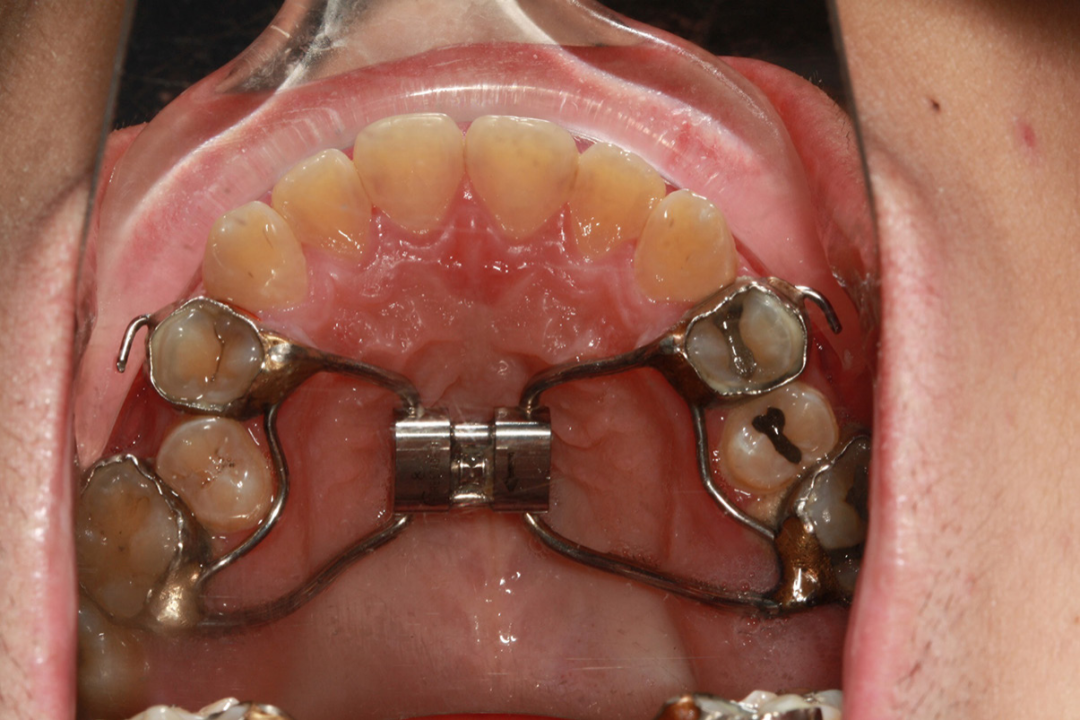

1、观察乳牙3、4、5牙冠的龋坏情况;牙齿曲断片上看乳牙3、4、5牙根吸收状况。若龋坏不严重可以治愈,或是牙根没有严重的吸收,则早期矫正干预方案是粘结式 RME配合前方牵引装置。

替牙期结束之后,进入年轻恒牙列阶段,此时若是前牙反颌,可以使用上颌带环式的RPE快扩配合前方牵引。RPE快扩能够激活上颌骨的邻接骨缝,促进上颌骨前移。